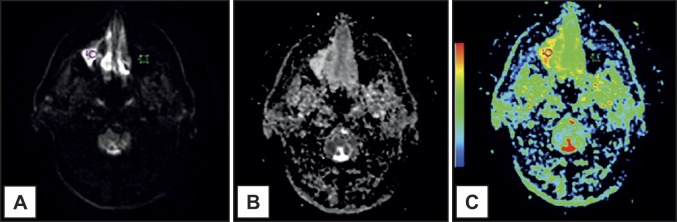

背景:磁共振成像被认为是诊断炎症性上颌窦疾病的较好影像学检查,可以提供精确的鼻窦特征。磁共振弥散加权成像与表观弥散系数是互补的磁共振成像工具,可用于鼻窦疾病的鉴别。本文报告3例炎症性上颌窦疾病结合弥散加权磁共振成像特征的影像学表现。此外,文献综述考虑使用扩散加权磁共振成像在炎性病变提供。方法:病例报告:存在气液水平,粘膜增厚和粘液潴留囊肿。常规磁共振成像和表观扩散系数(ADC)图,显示了ADC值。在文献综述中,详细介绍了考虑炎性病变的研究,以及研究者建立的ADC值。结果:气液水平、粘膜增厚和粘液潴留囊肿的ADC值分别为:1.99 x 10-3 mm2/s;1.83 × 10-3 mm2/s;2.05 × 10-3 mm2/s。结论:观察到本报告所描述的炎性病变的表观扩散系数值不同,表观扩散系数可用于鉴别这些上颌窦病变。进一步的大样本调查考虑明显的扩散系数值集中在炎性病变建议。缺乏考虑使用弥散加权磁共振成像诊断炎症性疾病的研究是文献综述的主要限制。

ABSTRACT Background Magnetic resonance imaging is considered a preferable imaging examination in the diagnosis of inflammatory maxillary sinus disease and can provide precise sinonasal characterization. Diffusion-weighted magnetic resonance imaging and apparent diffusion coefficient are complementary magnetic resonance imaging tools that can be applied to the differentiation of sinus diseases. In this report, 3 cases of inflammatory maxillary sinus diseases imaging findings considering diffusion-weighted magnetic resonance imaging features were described. Additionally, a literature review considering the use of diffusion-weighted magnetic resonance imaging in inflammatory lesions is provided. Methods The cases reported were: presence of air-fluid levels, mucosal thickening and a mucous retention cyst. Conventional magnetic resonance imaging and apparent diffusion coefficient (ADC) maps, with ADC values were demonstrated. In the literature review, the studies considering inflammatory lesions were detailed, as well as ADC values established by investigators. Results ADC values for presence of air-fluid levels, mucosal thickening and mucous retention cyst were respectively: 1.99 x 10-3 mm2/s; 1.83 x 10-3 mm2/s; 2.05 x 10-3 mm2/s. Conclusions It was observed that apparent diffusion coefficient values from the inflammatory lesions described in this report were different and apparent diffusion coefficient may be useful in the differentiation of these maxillary sinus alterations. Further larger sample investigations considering apparent diffusion coefficient values focusing in inflammatory lesions are recommended. The lack of studies considering the use of diffusion-weighted magnetic resonance imaging on inflammatory diseases diagnostic was the major limitation to the literature review.